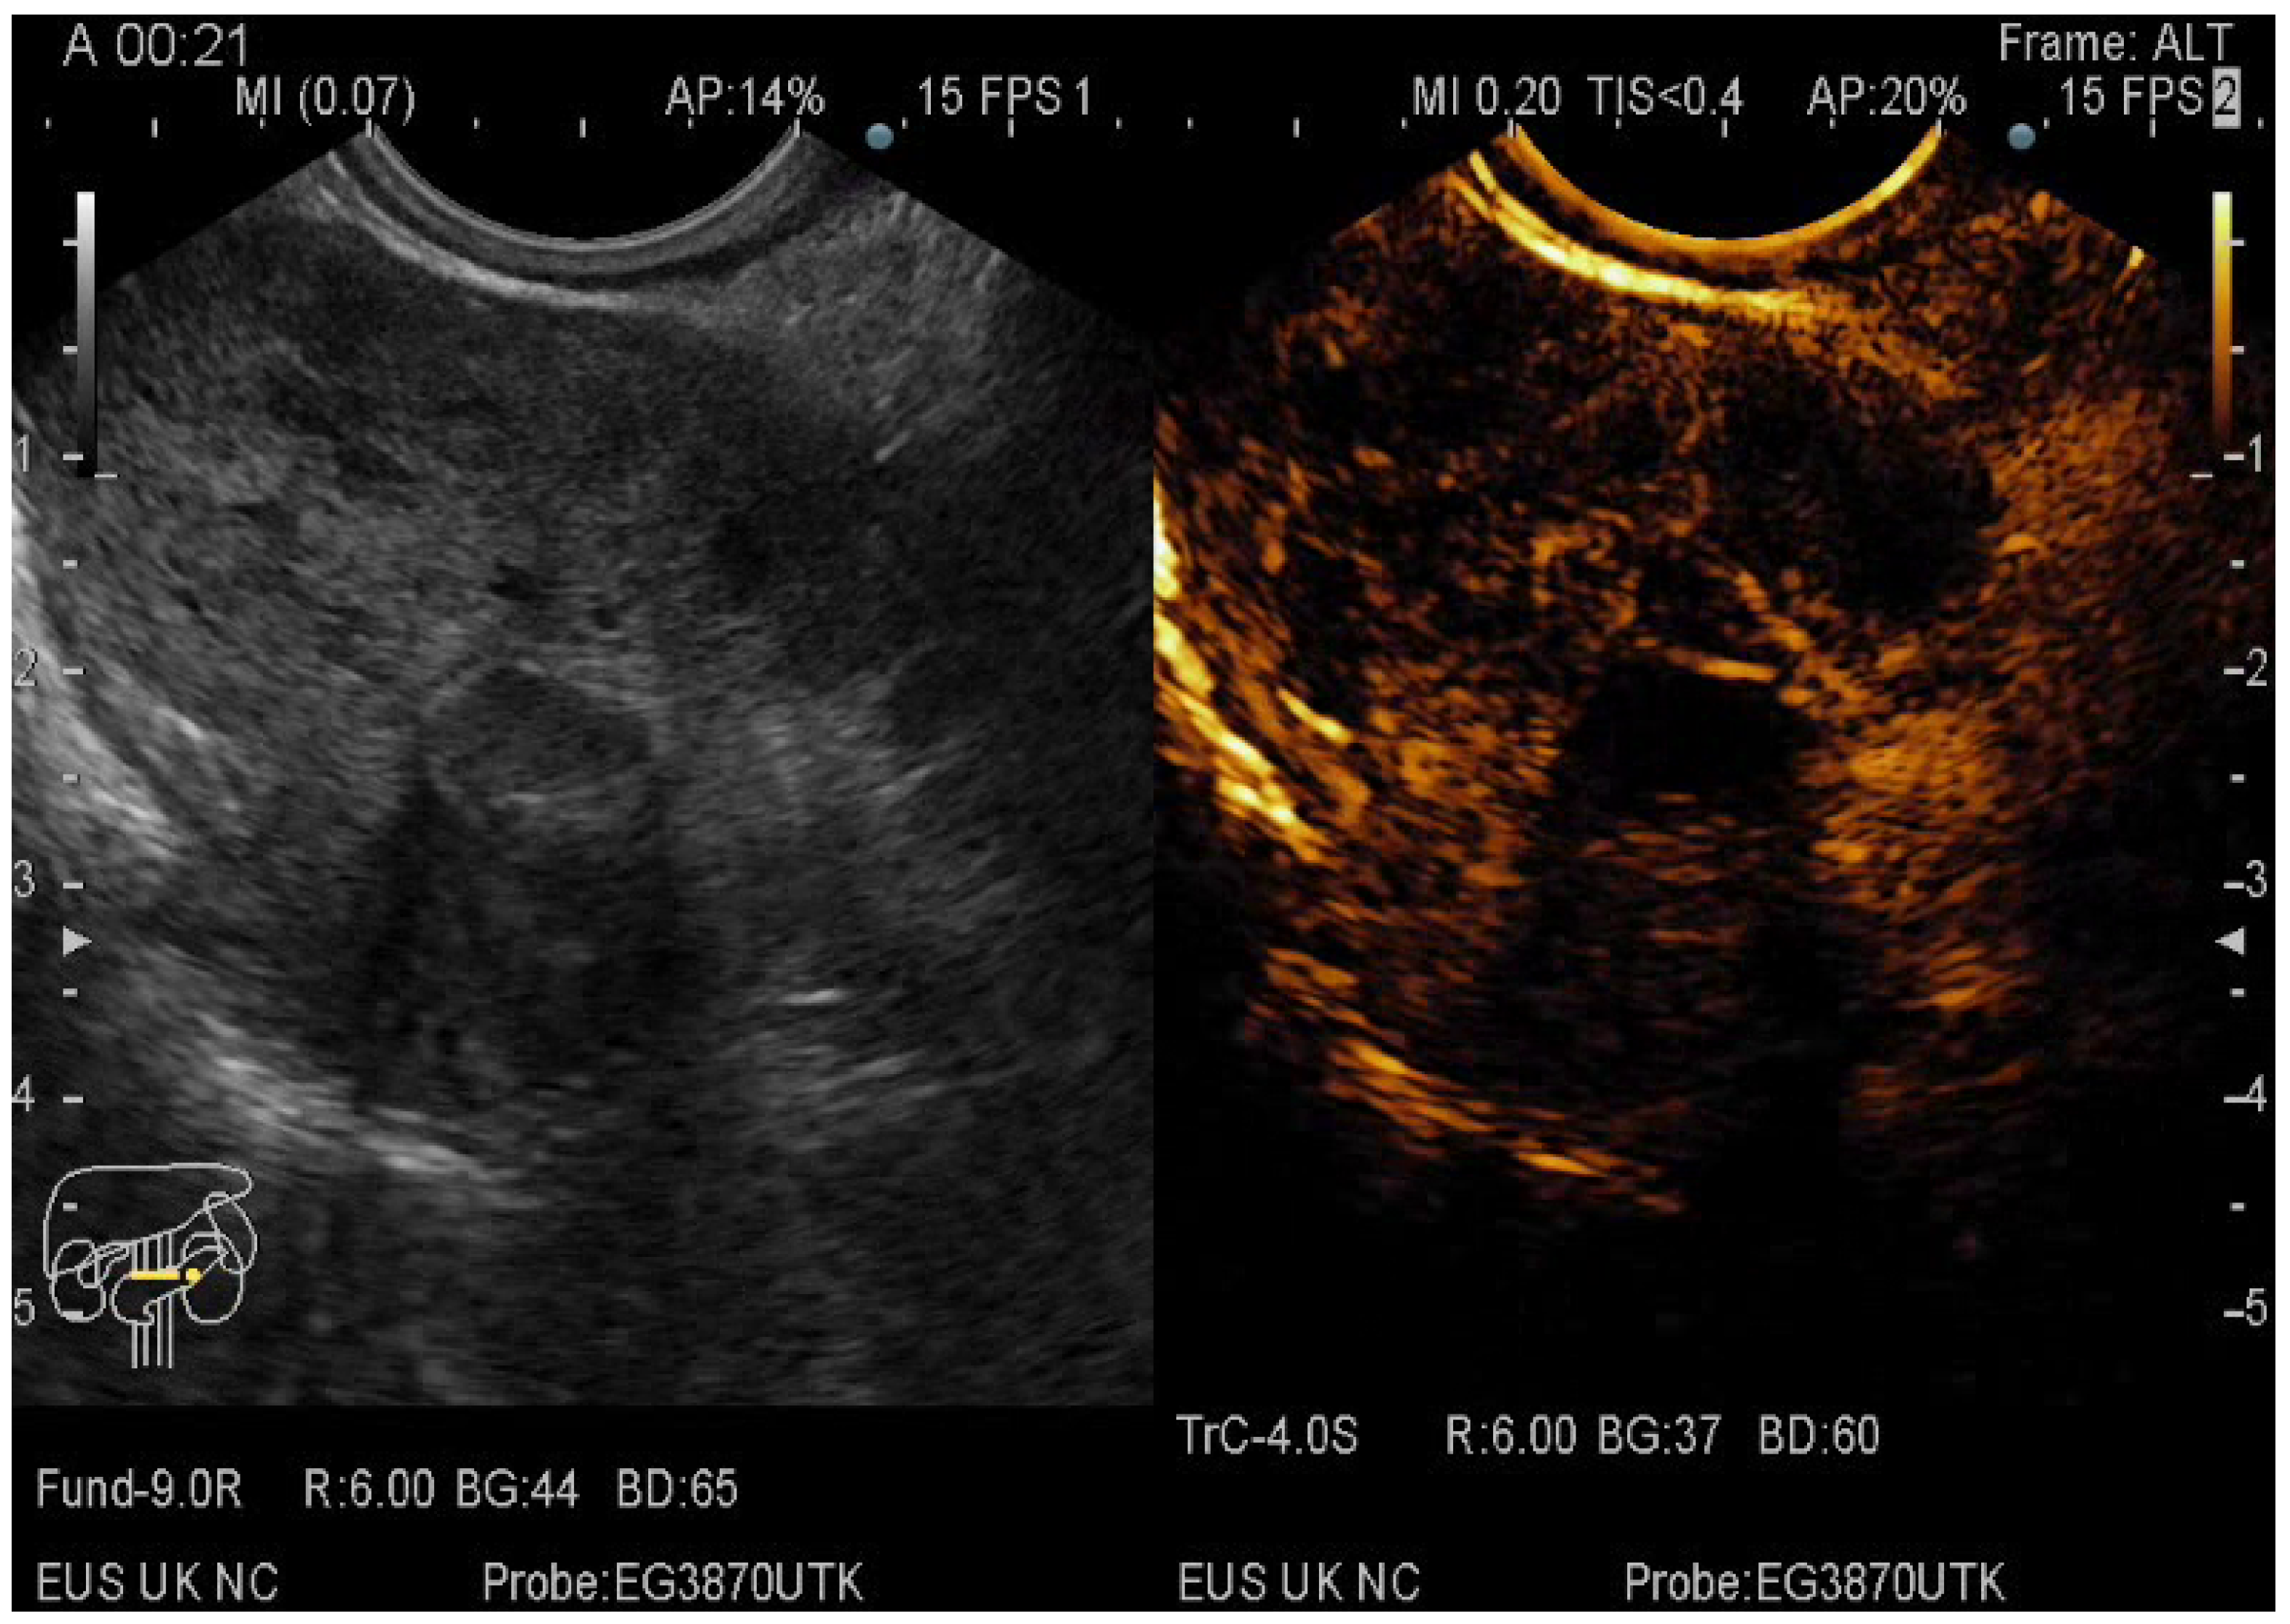

2.5. CE-EUS Procedure

- the entanglement of CE-EUS in describing pseudocysts and the benign/premalignant/malignant character of pancreatic cystic lesions

3.3. EUS-FNA/FNB + CE-EUS of Pancreatic Cystic Lesions Subgroup